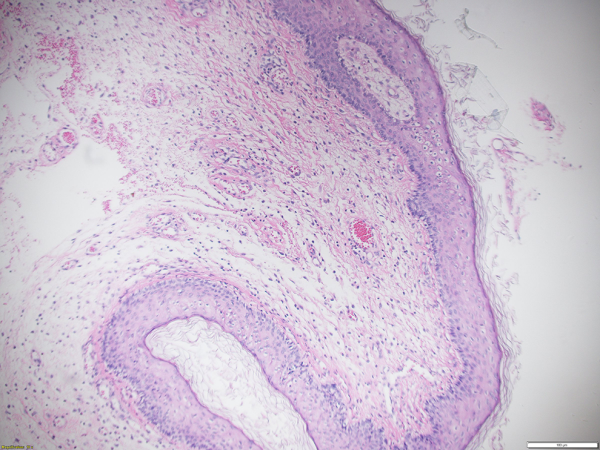

Figure 3

Histopathological findings of the fibroepithelial polyp with hematoxylin–eosin staining (×100 magnification).